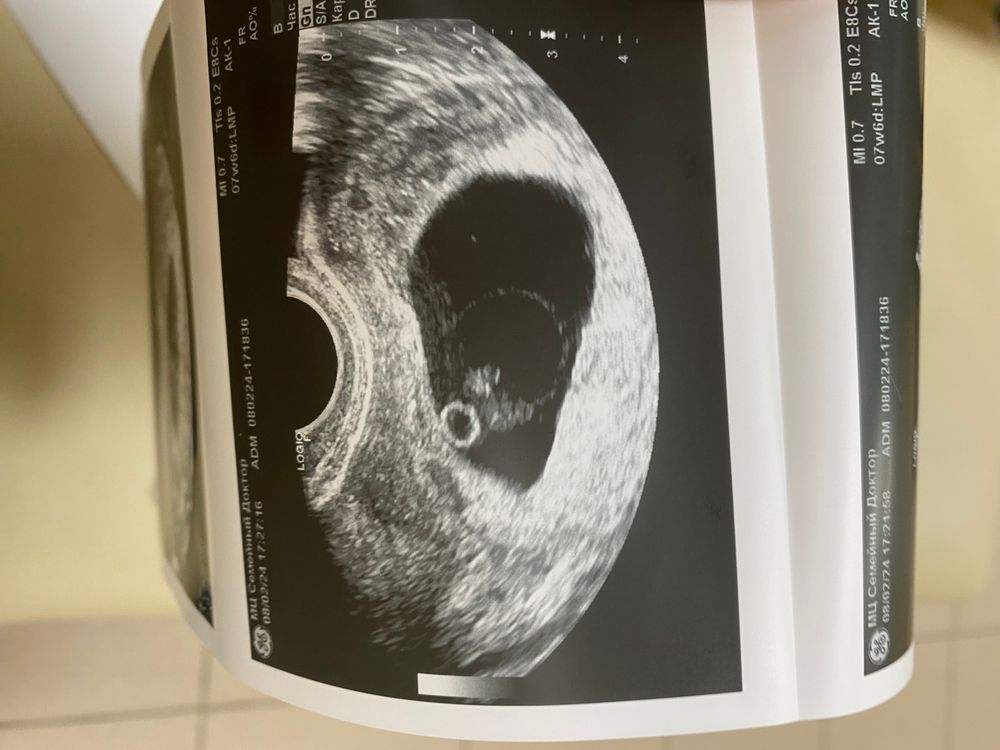

Слишком болшое плодное яйцо

ludarabaev, Изображение Изображение

какие размеры ПЯ и эмбриона? при таком хгч, это похоже на аномалию типа заноса, и в этом случае дальнейшая берем скорее всего невозможна, к сожалению. просто на данном снимке эмбрион даже не совсем правильных очертаний, либо это очень кривая проекция на узи

Дарья, я не знаю, не сказали. Но в 5 недель +4 было 19 мм